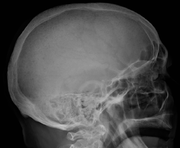

يُشخص المرض مخبريا بعمل عدة فحوصات و تشمل الفحوصات الوظيفية للكلية و قياس كمية الكالسيوم في الدم و عد مكونات الدم. و يستخدم الترحيل الكهربائي للبروتينات للتحري عن بعض البروتينات الغير طبيعية التي يتم إنتاجها بواسطة الخلايا السرطانية. للتحري عن أية كسور في العظام يتم تصوير المريض إشعاعيا بواسطة الجهاز الطبقي أو جهاز الرنين المغناطيسي.

X-ray of the forearm, with lytic lesions.

A CT of the brain revealed a lytic lesion in the left temporal bone (right side of image), and petrous temporal bones involving the mastoid segment of the facial nerve canal. Red arrows: lesion; green arrow: normal contralateral facial nerve canal. The lesions are consistent with a myeloma deposit.